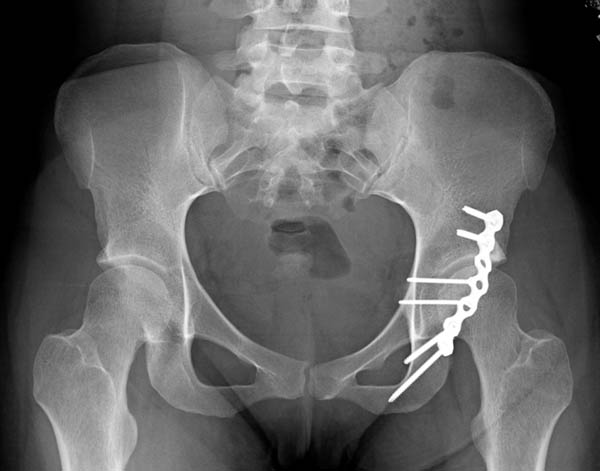

Коллеги! Хотелось бы посоветоваться по тактике лечения больного.Больной 24 лет, травму получил катаясь на горных лыжах. На рентгенограммах вертельный перелом. Но при детальном изучении снимков появилось подозрение на перелом головки бедра. Это побудило выполнить КТ. На КТ перелом заднего края вертлужной впадины.Планируем проксимальный стержень. А вот с вертлужной впадиной вопрос. Синтезировать или консервативно. "За операцию" внутрисуставной перелом, с вдавлением фрагмента суставной поверхности. "Против" смещенный фрагмент в задне-нижнем квадранте и в меньшей степени нагружаем... С ув Коробушкин Г.

Доступ классический Kocher-Langenbeck, который позволит из одного доступа зафиксировать перелом вертлужной впадины и чрезвертельный перелом бедра. При этом варианте вопрос фиксатора для бедра не имеет значения, подойдет любая пластина для проксимального бедра или гвоздь!

5 Ap pelvis postop.jpg